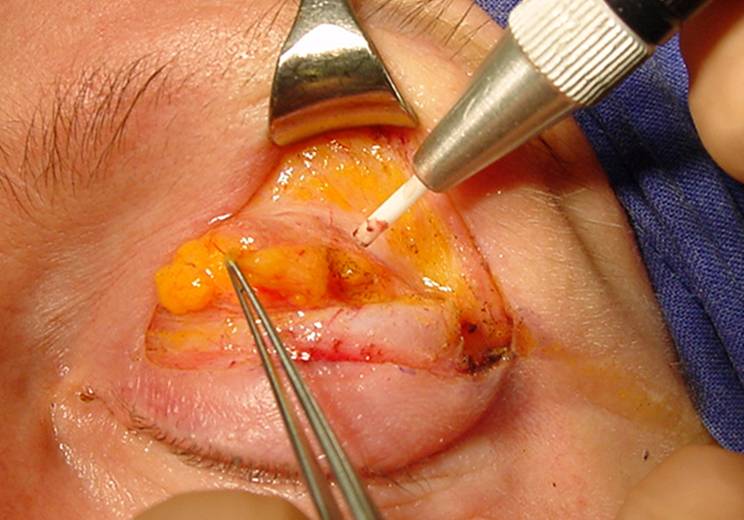

Tras haber abierto el septo se expone la grasa orbitaria, dicha grasa se puede reducir en su volumen en aquellos casos en los que inhiba la formación del surco y del pliegue.

La grasa orbitaria se divide en varios compartimientos, la central, la intermedia y la medial. Se pueden reducir en su volumen o transponer para formar el surco deseado.

![]() |

Fig.5: M= grasa medial I= grasa intermedia C= grasa central Gl= glándula lagrimal |

Fig.6: Acceso a la grasa medial con el láser CO2 |